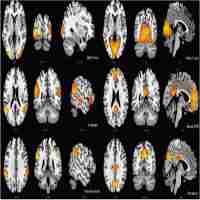

Altered resting‐state functional network connectivity in profound sensorineural hearing loss infants within an early sensitive period: A group ICA study

| Subject Keyword | Journal: Human brain mapping Otorhinolaryngology Functional Connectivity Independent Component Analysis Resting-state Network Sensorineural Hearing Loss |